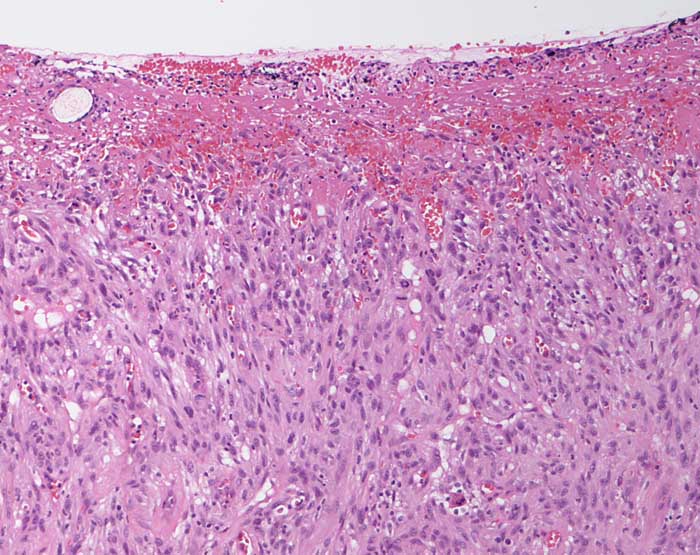

atypisches Fibroxanthom

maligner Tumor

Haut, Kopf

Breitflächig ulzerierter spindelzelliger Tumor mit einzelnen Mitosen und mässiggradiger Zellpleomorphie.

Ulzerierter Tumor am Kopf.

Oberflächliche Variante des malignen fibrösen Histiozytoms. S-100 und Zytokeratin negativ.

Histologie

100